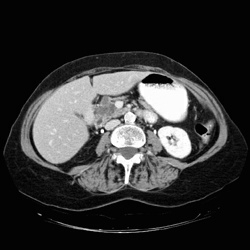

RADIOLOGY: PANCREAS: Case# 33079: AML & PANCREATIC MASS. This is an 83-year-old female complaining of one month of abdominal pain and hard stools. 1. Mass in the head of the pancreas, containing multiple cystic structures. This is most probably benign as it does not appear to invade adjacent structures and does not compress or obstruct the duct. This is probably a microcystic adenoma, without malignant potential. 2. Multiple splenic lesions. These are very small, and are indeterminate. They possibly represent hemangiomas, abscesses or cysts, but are unable to be determined by this exam. 3. Angiomyolipoma of the right kidney.4. Bartholins gland cyst.